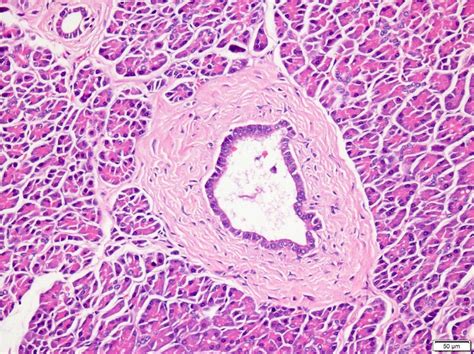

The pancreas is located in the abdomen, behind the stomach, and is composed of both exocrine and endocrine tissues. The exocrine portion produces enzymes that aid in digestion, while the endocrine portion produces hormones like insulin and glucagon, which regulate blood sugar levels. The pancreatic ductal system is responsible for transporting these enzymes and hormones to their respective destinations.

The Accessory Pancreatic Duct is a smaller duct that runs parallel to the main pancreatic duct, known as the duct of Wirsung. It drains a portion of the pancreatic enzymes into the duodenum through the minor duodenal papilla. This duct is particularly important in cases where the main pancreatic duct is obstructed or damaged, as it provides an alternative pathway for pancreatic secretions.